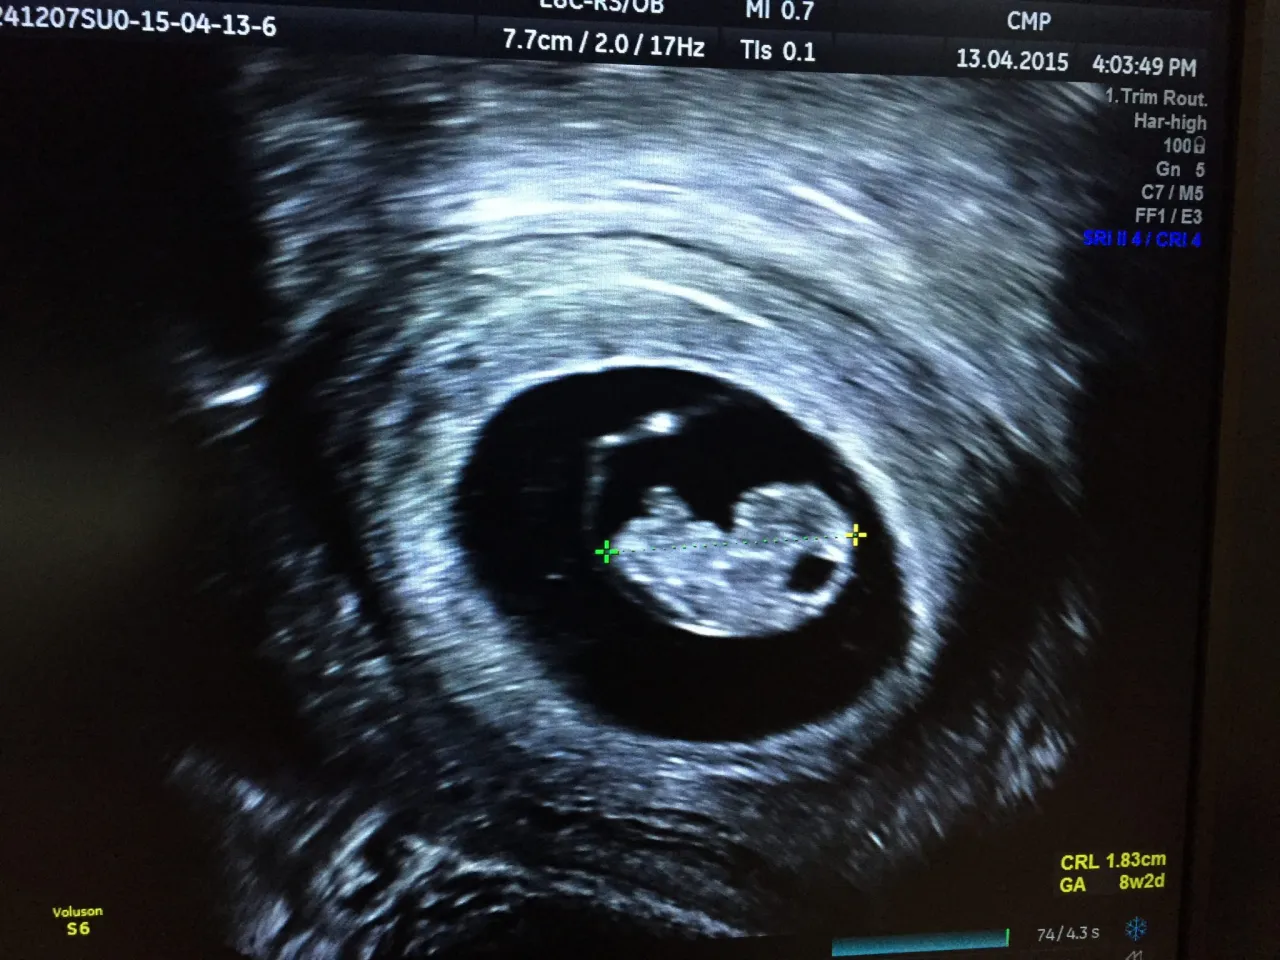

- Ostateczne potwierdzenie ciąży następuje u ginekologa, najczęściej między 6. a 8. tygodniem ciąży, gdy widoczne jest tętno zarodka.

Ostateczne i 100% pewne potwierdzenie ciąży następuje podczas wizyty u ginekologa. Lekarz przeprowadzi badanie USG, podczas którego będzie mógł zobaczyć pęcherzyk ciążowy, a w późniejszym etapie zarodek i jego akcję serca. Ta wizyta jest kluczowa nie tylko dla potwierdzenia ciąży, ale także dla oceny jej prawidłowego rozwoju, określenia wieku ciąży i zaplanowania dalszej opieki prenatalnej. To ważny moment, który rozpoczyna drogę do macierzyństwa.

Optymalny czas na pierwszą wizytę u ginekologa to okres między 6. a 8. tygodniem ciąży, licząc od pierwszego dnia ostatniej miesiączki. W tym czasie lekarz będzie w stanie wykonać badanie USG, podczas którego zazwyczaj widoczny jest już pęcherzyk ciążowy, zarodek, a co najważniejsze akcja serca zarodka. Wcześniejsza wizyta, np. w 4-5 tygodniu, może być niejednoznaczna. Pęcherzyk ciążowy może być już widoczny, ale zarodek i jego tętno jeszcze nie, co może niepotrzebnie wywołać niepokój. Poczekanie do 6-8 tygodnia zwiększa szansę na pełen obraz sytuacji i uspokojenie.